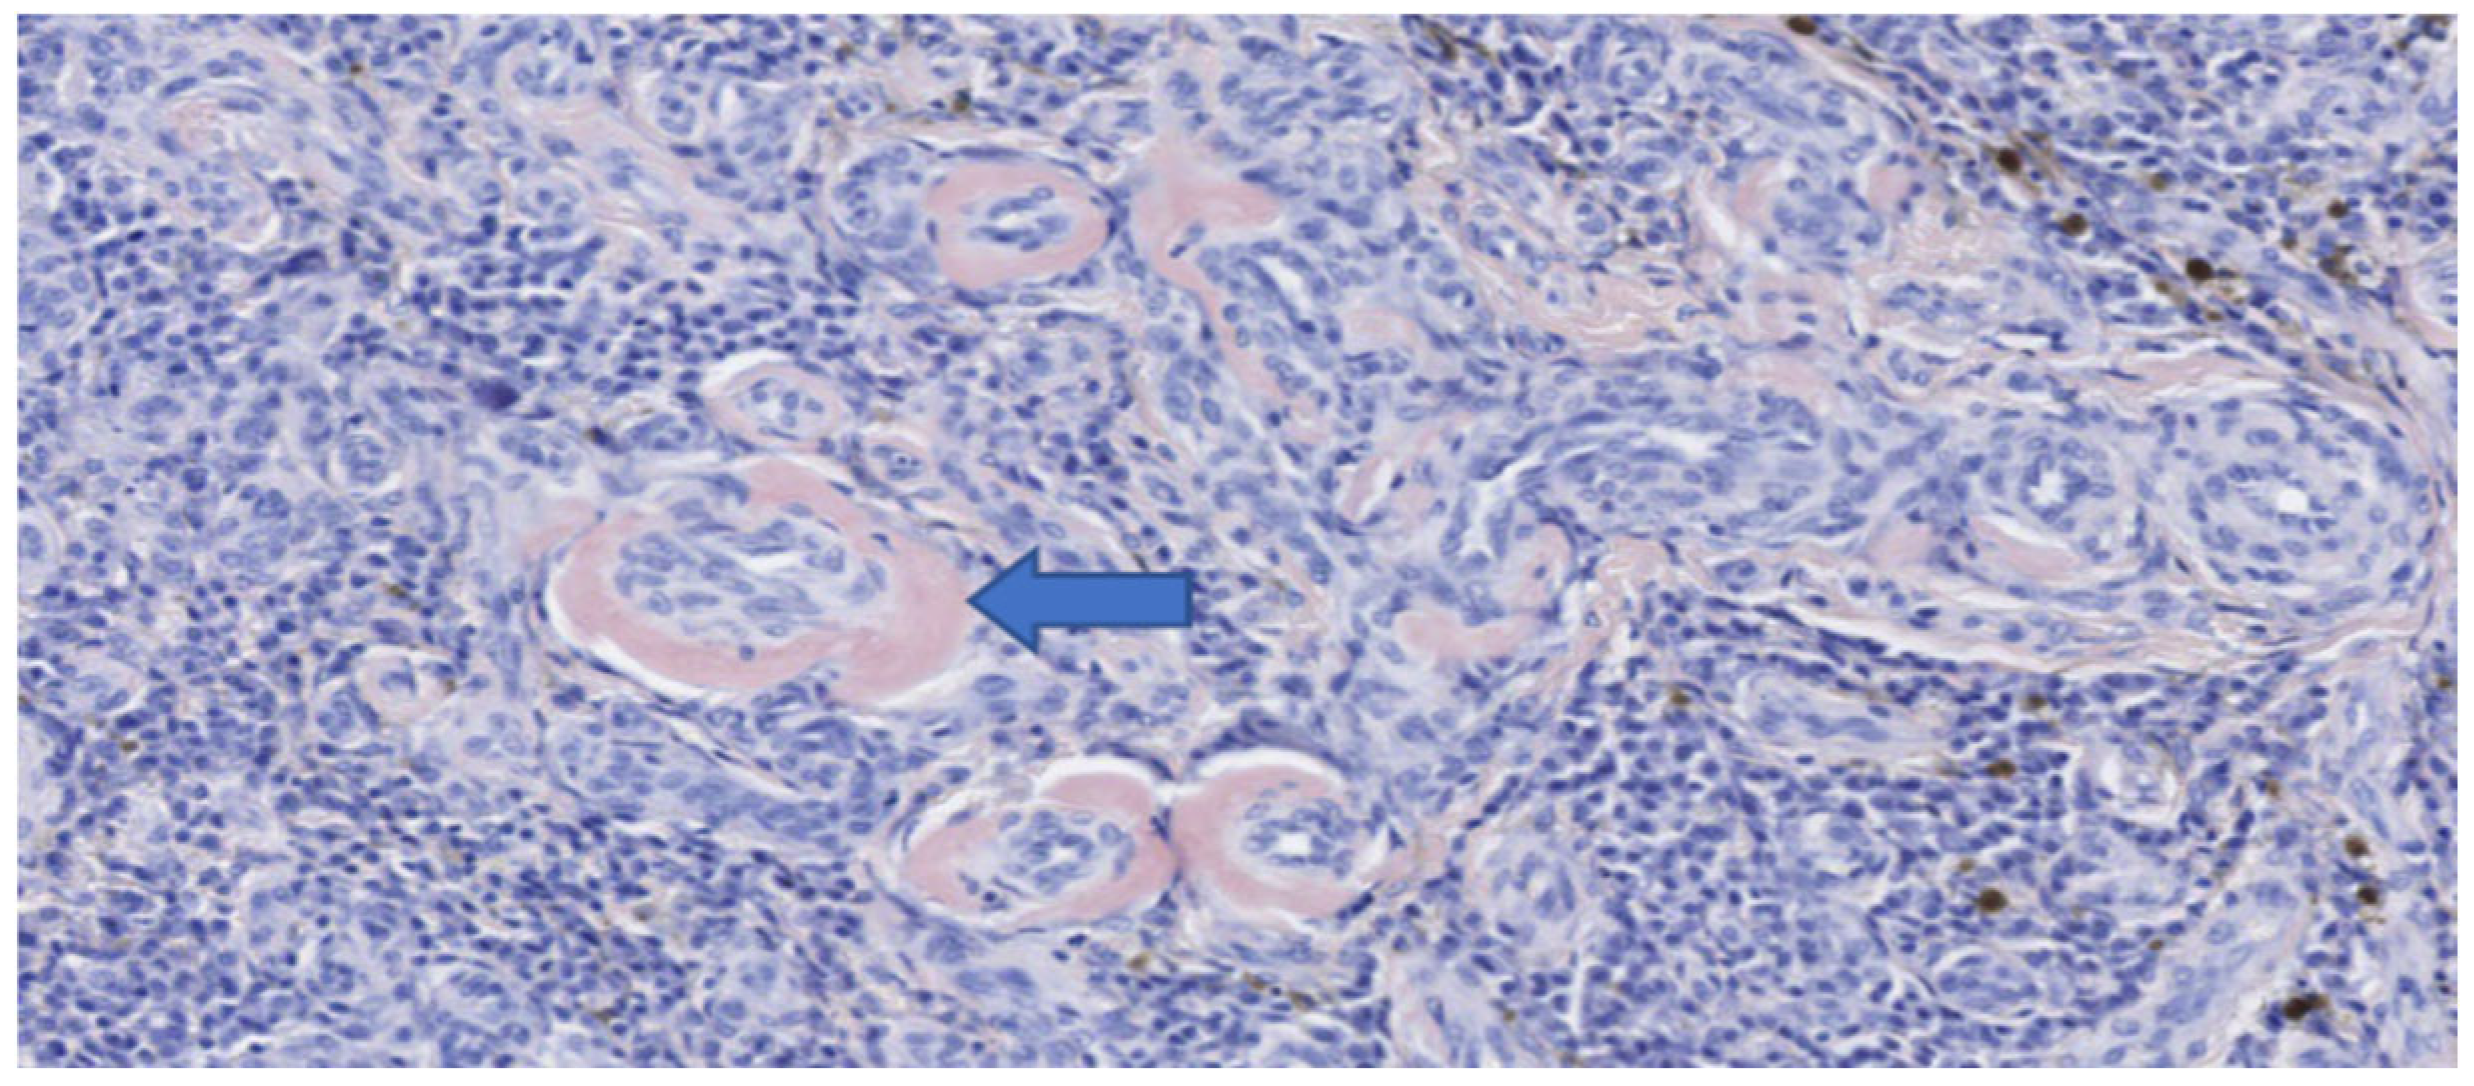

The mass measured approximately 7 cm in length (Figure 6). Histopathological and immunohistochemical examination of the mass revealed that despite the abundant necrosis and hemorrhage, there was a neoplastic proliferation of plasma cells with extracellular amorphous eosinophilic material interpreted as amyloid based on Congo red staining (Figure 7 and Figure 8). Therefore, a diagnosis of a plasma cell tumor with perivascular amyloid deposition was made. This diagnosis was confirmed by immunohistochemistry (IHC) with a monoclonal anti-multiple myeloma oncogene 1 (MUM-1) antibody (clone MUM1p, Catalog #GA64461-2, Dako Omnis, Agilent, Richmond, VI, USA) (Figure 9).

Figure 8.

Histopathology of the esophageal mass after surgical excision (Congo red stain). Positive intramural accumulations of amyloid (blue arrow).

Figure 9.

Immunohistochemistry of the esophageal mass after surgical excision (MUM-1 stain). High power view of positive plasma cells and intralesional amyloid deposits.